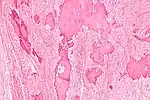

| Low magnification micrograph of a calcified ovarian fibroma in the context of nevoid basal cell carcinoma syndrome. H&E stain. | |

On gross pathology, they are firm and white or tan. On microscopic examination, there are intersecting bundles of spindle cells producing collagen.

Diagnosis is usually made by ultrasonography showing a solid ovarian lesion, or, on some occasions, mixed tumors with solid and cystic components.[1] Computed tomography and magnetic resonance imaging can also be used to diagnose fibromas. In a series of 16 patients, 5 (28%) showed elevated levels of CA-125.[1] Histopathology demonstrates spindle-shaped fibroblastic cells and abundant collagen.[3]